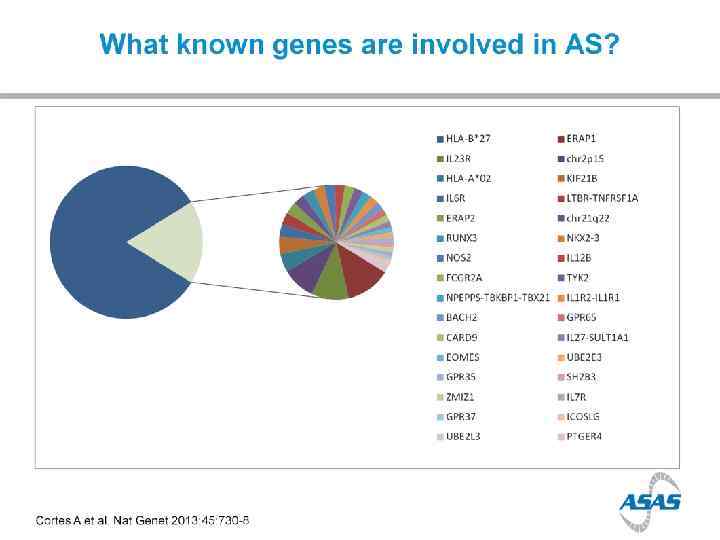

HLA B 27 1970 s HLA B 27 + in 90% of Caucasian AS pt Only 5% of HLA B 27+ persons will have AS HLA B 27 represents only about 25% of ‘genetic risk’ for AS